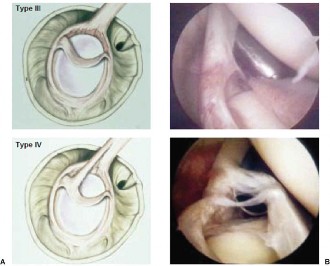

The correct answer is (B). The Snyder classification of SLAP tears is the first widely used classification systems for SLAP tears and consists of types I to IV (see Fig. 2–22A–B and Table 2–3). In type I tears (Answer A), there is fraying of the glenoid edge of the superior labrum, but the biceps tendon and superior labrum are both firmly attached to the biceps anchor and glenoid edge. In type II tears (Answer B), the biceps tendon and the superior labrum are detached from the superior glenoid edge and biceps anchor. In type III tears (Answer C), there is a bucket-handle tear of the superior labrum, but the remainder of the superior labrum and biceps tendon remain firmly attached to the glenoid rim and biceps anchor. In type IV tears (Answer D), there is a bucket-handle tear of the superior labrum that extends into the biceps tendon with extension of parts of the labral flap or biceps tendon into the joint space, and the remainder of the labrum and biceps tendon remain firmly attached to the glenoid rim and biceps anchor. Type V tears (Answer

Figure 2–22(A–B) Snyder classification of rotator cuff tears in cartoon and arthroscopic views. (From Mileski RA, Snyder SJ. Superior labral lesions in the shoulder: pathoanatomy and surgical management. J Am Acad Orthop Surg. 1998;6(2):121–131.)